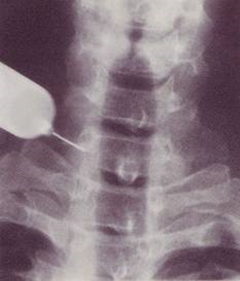

図.星状神経節ブロックのレントゲン像です。